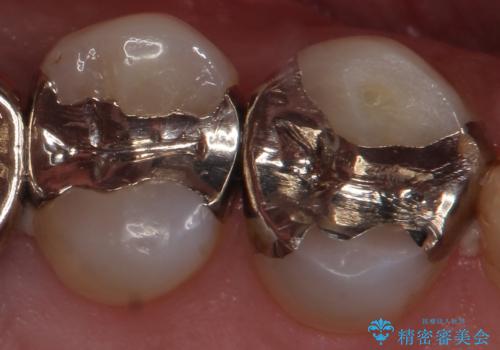

外から見える銀歯 セラミックでのやり替え

- 笑った時にチラつく銀歯が気になるから白くしたいとのことで来院。

銀の詰め物を除去し、残った歯の量が多かったためセラミックインレーでの修復となりました。

- 右上56 セラミックインレー 77000円×2本費用は治療当時の料金となります

また今回は治療前の写真で食べ物が詰まっている様子が伺えますが、適合がよく段差のない修復をすることで食べ物が詰まることを減らし、結果的に虫歯のリスクを下げることも期待できます。